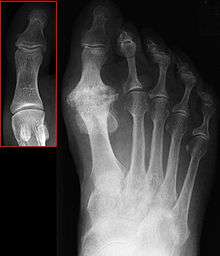

| Hallux not labeled but visible at upper left. | |

Hallux rigidus or stiff big toe is degenerative arthritis and stiffness due to bone spurs that affects the MTP joint at the base of the hallux (big toe).

In 1988, Hattrup and Johnson described the following radiographic classification system: Grade I - mild changes with maintained joint space and minimal spurring. Grade II - moderate changes with narrowing of joint space, bony proliferation on the metatarsophalangeal head and phalanx and subchondral sclerosis or cyst. Grade III - Severe changes with significant joint space narrowing, extensive bony proliferation and loose bodies or a dorsal ossicle.[3]